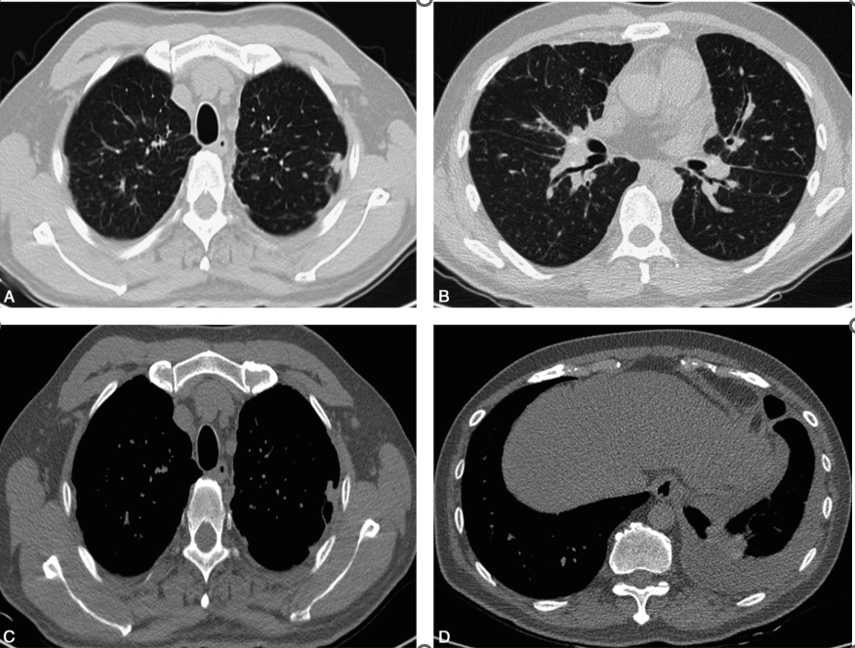

胸部CT平扫(2017-04-28,图1):双肺肺门及支气管血管束中央间质增生,小叶间隔增厚,双侧肺野弥漫性细小结节影;双侧胸膜局限性增厚及多发结节影;左侧少-中量胸腔积液;冠脉支架植入术后;心包少量积液。

图1胸部CT平扫:肺窗(A、B)示双肺弥漫细小结节影,小叶间隔增厚,中央间质增生;双上肺胸膜下结节影,以左上肺为著;纵隔窗(C、D)示左侧胸膜不规则增厚伴结节影,左侧少-中量胸腔积液